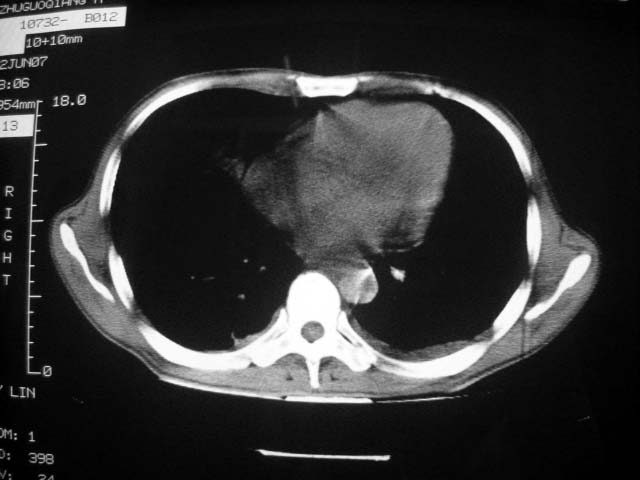

前几次大家认为是转移癌,但此次复查病灶却明显吸收好转,不支持诊断。请大家讨论。[emb10]

继发性tb,双侧胸腔积液,原来的在哪?

双侧继发性肺结核伴两肺播散灶.双侧胸腔少量积液

近2个月病灶变化较大,应是感染性病变,首先考虑金黄色葡萄球菌感染。

根据前后片比较应该考虑迁徙性肺脓肿,回帖相差甚远是因为前后片变化太大出乎大家意料之外,这就是影象诊断要结合临床复查对比的必要性,

回顾既往片,病变明显吸收,缩小,未经治疗,不支持肺转移瘤,可能为肺结节病或韦格氏肉芽肿